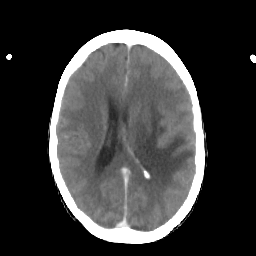

Metastatic bronchogenic carcinoma: Roentgen-ray CT -- Slice #13

[Home][Help][Clinical] Slice 13